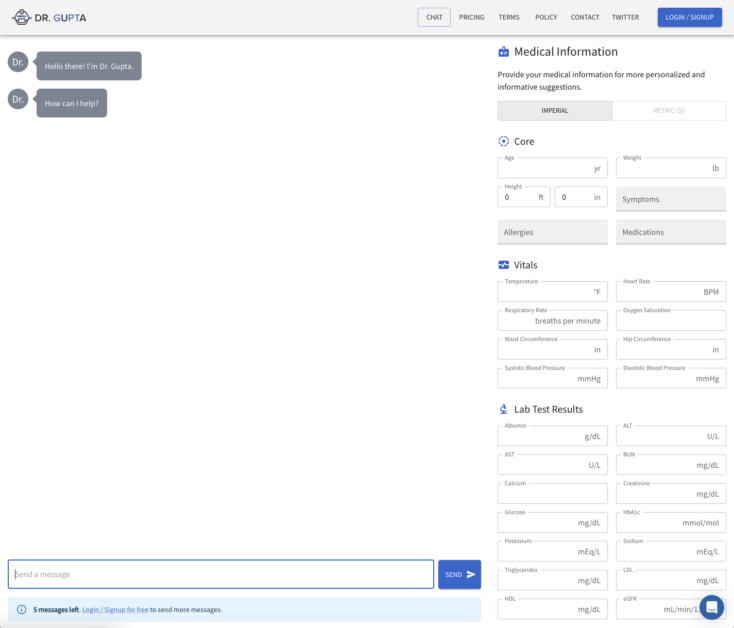

Dr Gupta takes its name from the underlying technology powering the bot, ChatGPT. OpenAI’s technology has created various new AI bots, Dr Gupta uses a modified version that can understand complicated medical questions. Dr Gupta can also enhance its answers by users providing their medical information such as; age, weight, height, temperature, heart rate, and much more.

Dr Gupta allows 10 free messages a month. After that, there is a single paid option for $20/month which gives full access to the site, unlimited messages, early access to new features, and an ad-free experience.